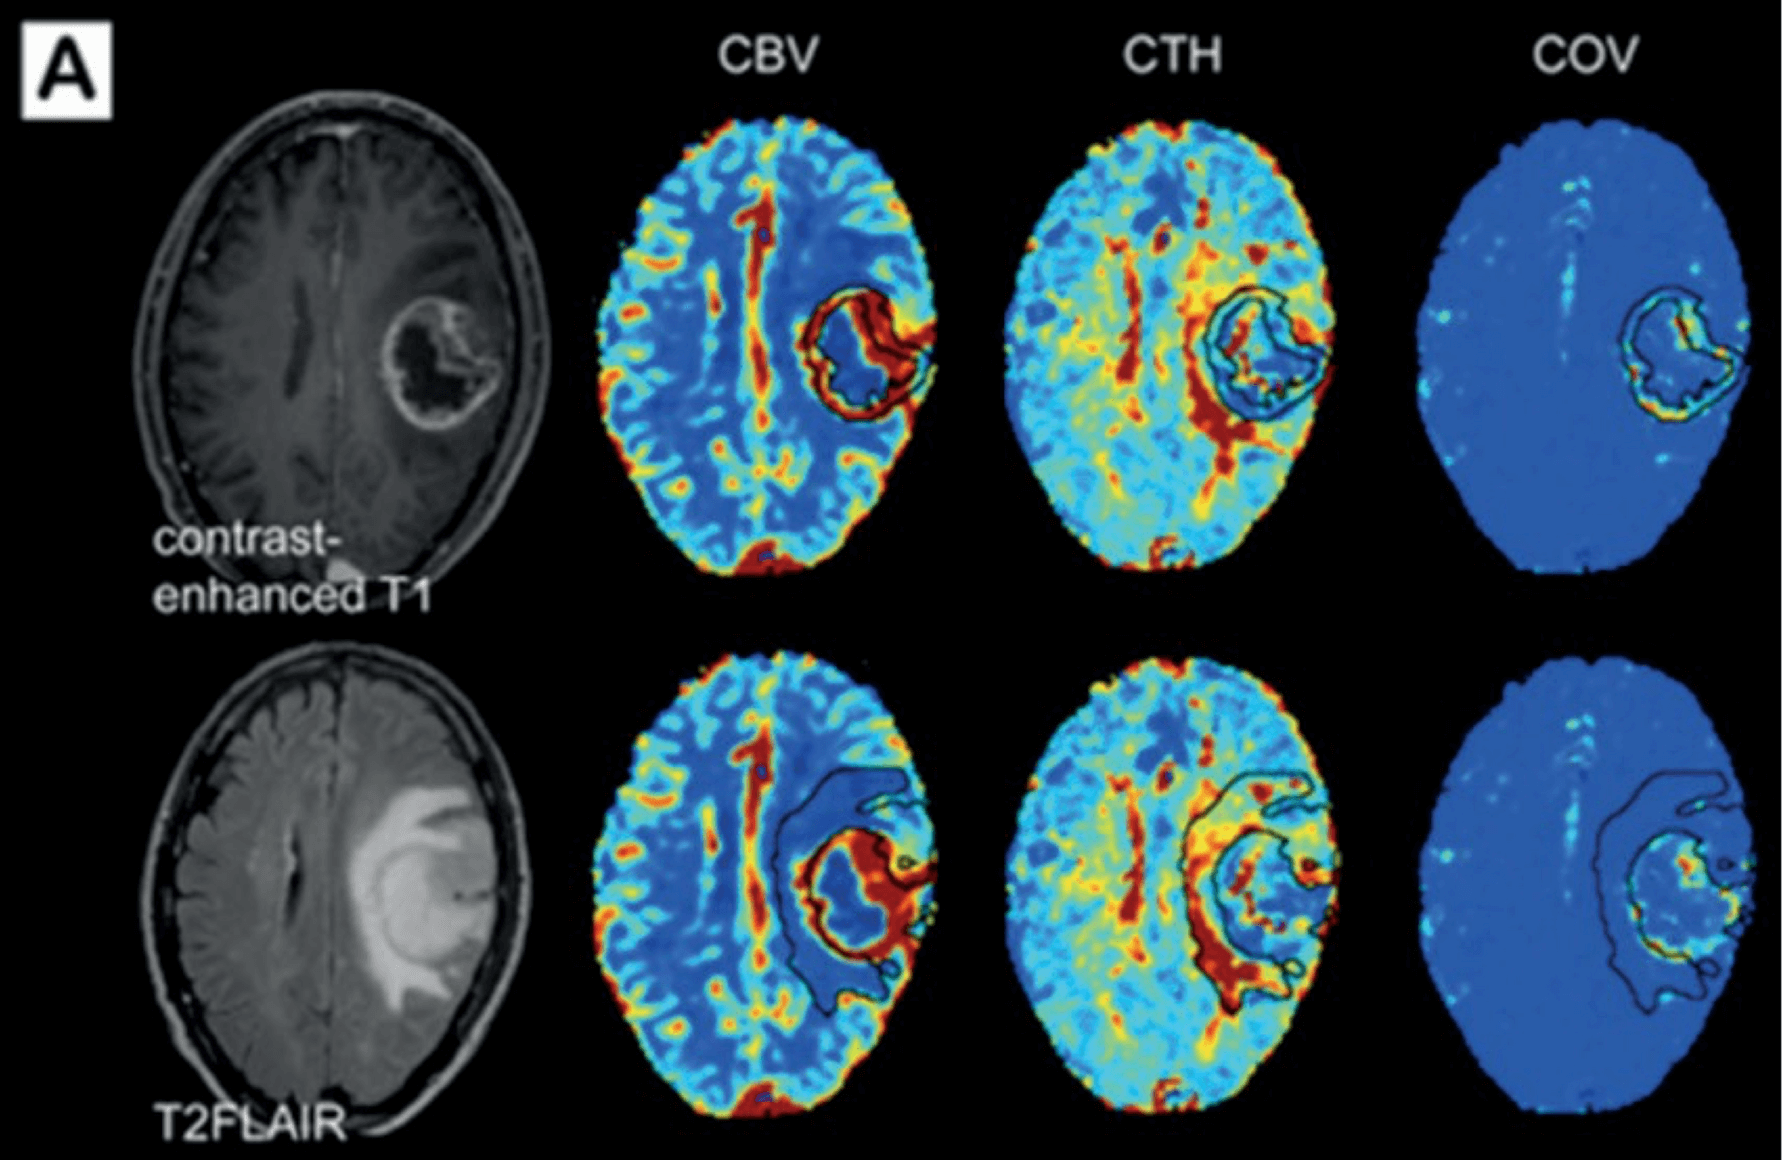

PROPRIETARY BIOMARKERS FOR NEURO-ONCOLOGY

Vascular Biomarkers

- CTH Capillary Transit Time Heterogeneity.

- COV Microvascular Coefficient of Variance.

- Leakage Blood-Brain Barrier Integrity.